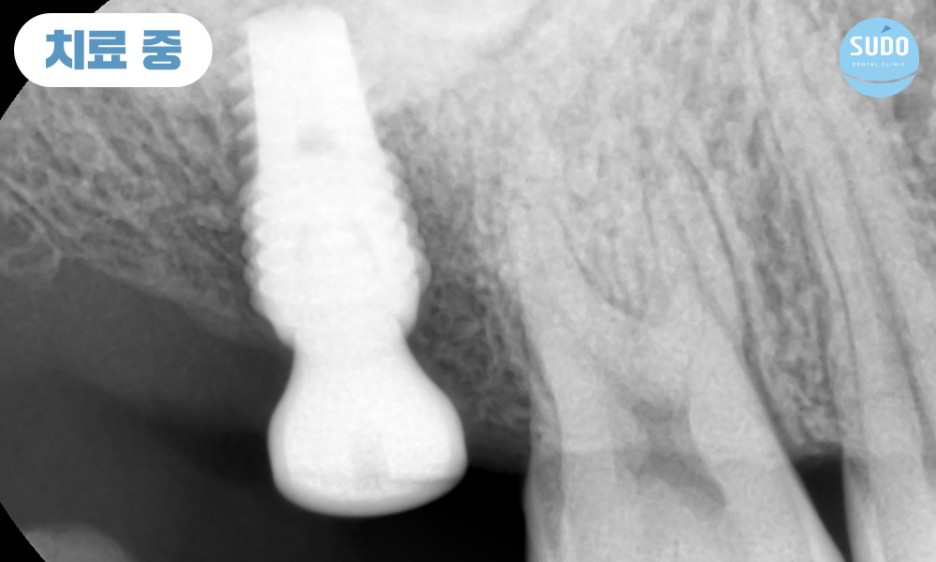

식립 당일 힐링 어버트먼트를 결합한 채로 본래의 잇몸뼈와 안정적으로 융합될 수 있도록 충분한 기간 동안 기다려주었습니다.

힐링 어버트먼트란, 임플란트를 보호하고 잇몸 조직의 적절한 치료를 촉진하며 미관을 개선하고 최종 보철물의 배치를 위한 안정적인 기준을 제공하기 위한 목적으로 사용합니다.